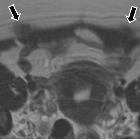

There is a predilection for right-sided involvement in case of pleural endometriosis, however in parenchymal involvement there is no such predilection seen.

HRCT is the modality of choice for thoracic endometriosis, which may demonstrate presence of pneumothorax, hemothorax or nodules which may change in nature cyclically. There may sometimes be vague areas of bronchial wall thickening, thin-walled cavities, bullous formation or ground glass opacities. HRCT may also be used to provide guidance for targeted biopsy. Imaging should be carried out during menstruation for higher sensitivity.